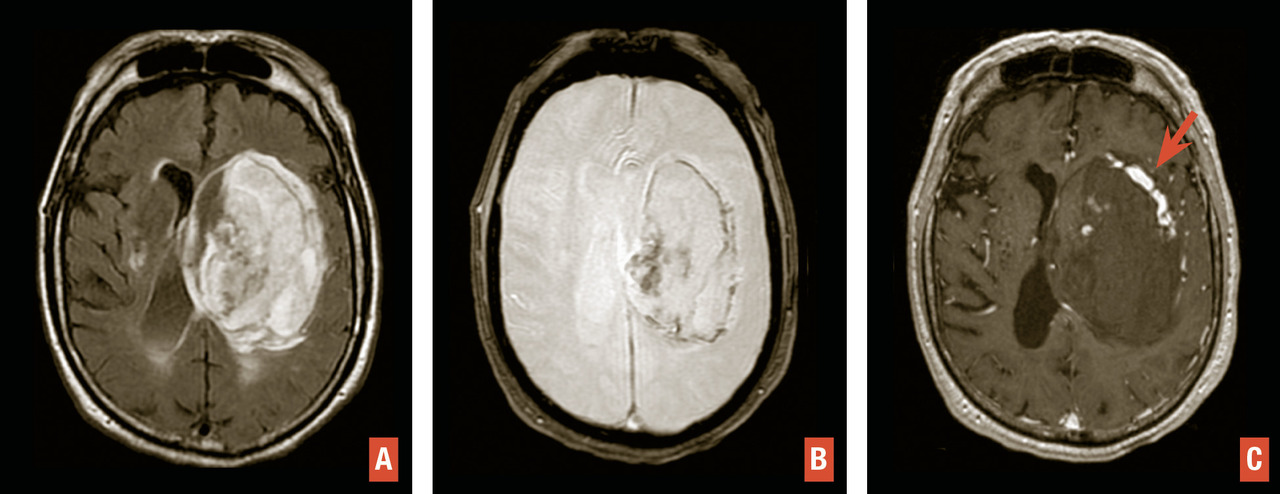

En TDM comme en IRM, l’hématome cérébral se traduit par une masse, de volume et de topographie variables, avec œdème périlésionnel. En tomodensitométrie, l’hématome aigu est hyperdense spontanément. En IRM, il est hyperintense en séquence T2/FLAIR avec hyposignaux le plus souvent périphériques en T2* (fig. 5 ). L’aspect hétérogène, la présence d’îlots hématiques satellites et le « spot sign » visible après injection traduisent un saignement actif avec risque de majoration rapide en volume (fig. 6 ).